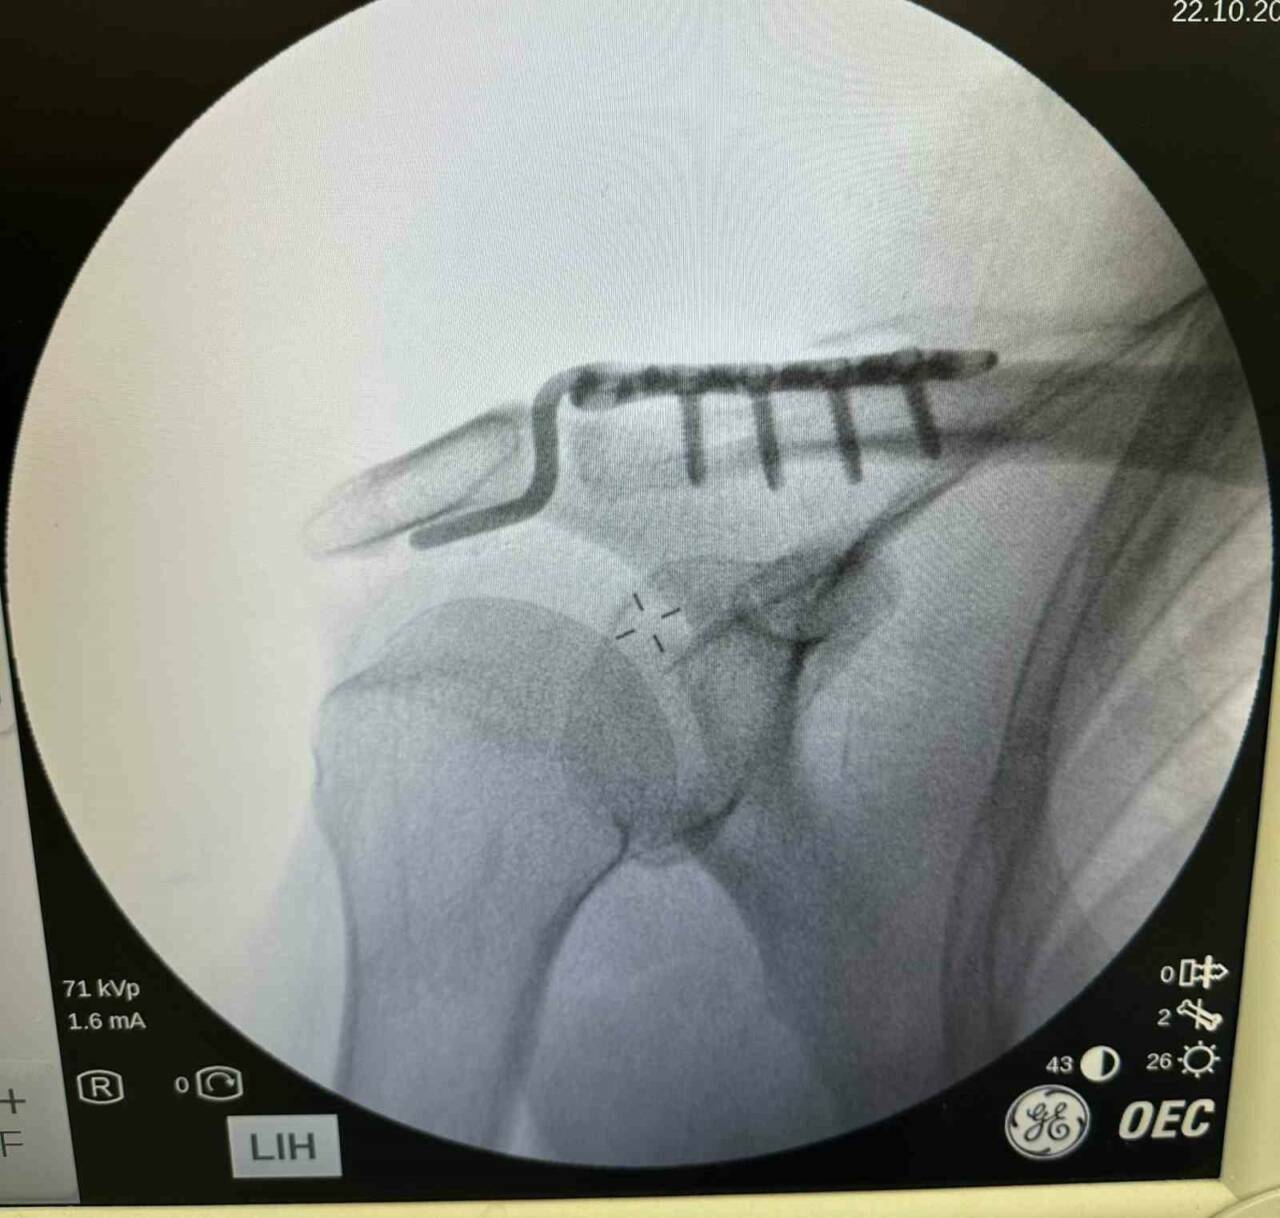

Batman’da 64 yaşındaki Mehmet Şerif Rençber, tenis oynarken omuz çıkığı yaşadı. İleri yaş nedeniyle ameliyat olamayacağı söylense de, Dr. Mehmet Yavuz Başer özel bir plak kullanarak başarılı bir ameliyat gerçekleştirdi. Rençber, ameliyat sonrasında ağrısız bir şekilde eski omuz hareketlerine geri döndü. Hastanın yaşadığı iyileşme, doktorun özenli ve başarılı müdahalesi sayesinde gerçekleşti.

BATMAN’DA, TENİS OYNARKEN OMUZ ÇIKIĞI YAŞAYAN 64 YAŞINDAKİ MEHMET ŞERİF RENÇBER, İLERİ YAŞ NEDENİYLE AMELİYAT OLAMAYACAĞI, KENDİLİĞİNDEN İYİLEŞECEĞİ CEVABI OLMASINA RAĞMEN BAŞKA BİR DOKTORUN ÖZEL PLAK KULLANARAK AMELİYAT ETMESİYLE SAĞLIĞINA KAVUŞTU.

DR. MEHMET YAVUZ BAŞER, HASTANIN 64 YAŞINDA OMUZ ÇIKIĞI NEDENİYLE KENDİLERİNE BAŞVURDUĞUNU SÖYLEDİ.